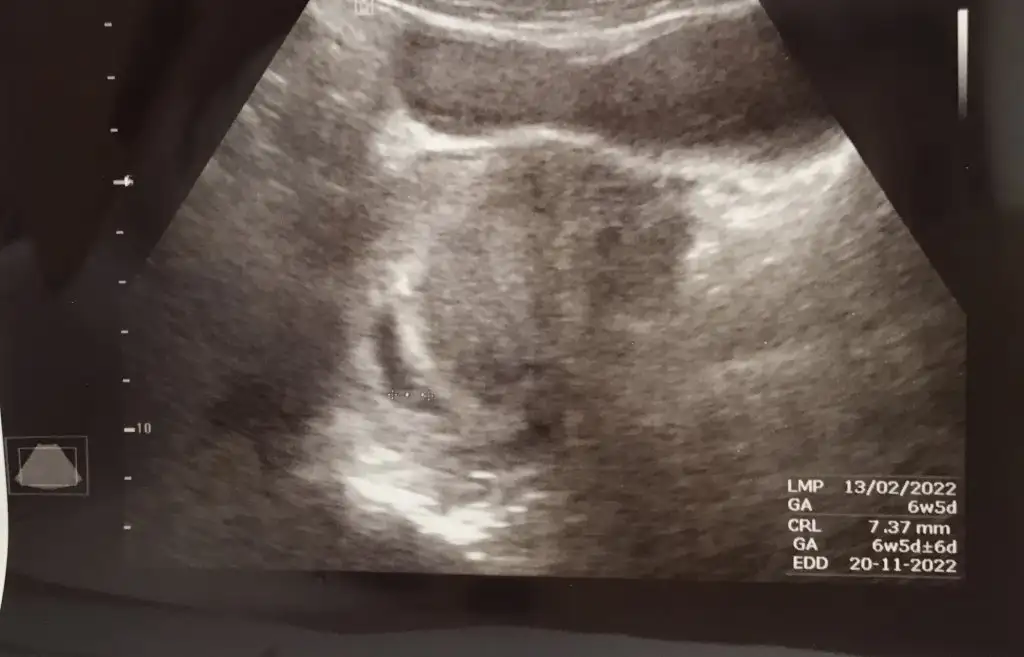

Bu bir kiz bebek.Şu an yanımda değil ama aynı şu şekild

Esimin doğum tarihi net değil canım, ben kendim çin takviminden baktım erkek gösteriyor. Büyük oğlum da tutmuştu bakalım sağlıklı olsun yeterliBu bir kiz bebek.

Valla benim için herkes erkek demişti sivriymiş baya kız olmuşum çokta şaaapmayın sağlıklılı olsun yeterKızlar bı arkadaş keseye göre tahmin yapıyor ve hep tutuyormuş iki oğlunu da bu şekilde cok yeniyken bile tahmin etmiş...ogullarinda kesesi hep uzunmuş muz gibi...yuvarlak ve yuvarlağa yakın olanlar hep kızdır diyor..ve bayağı emin konusuyor..benimki şişman bı fasulye gibi oo kesin kız görürsün dedi...sizlerin keselerinin şekli nasıldı ve cinsiyet neydi konusalimmi![]()

Benim ultrasonumuda yorumlarmısınız rica etsemBu bir kiz bebek.